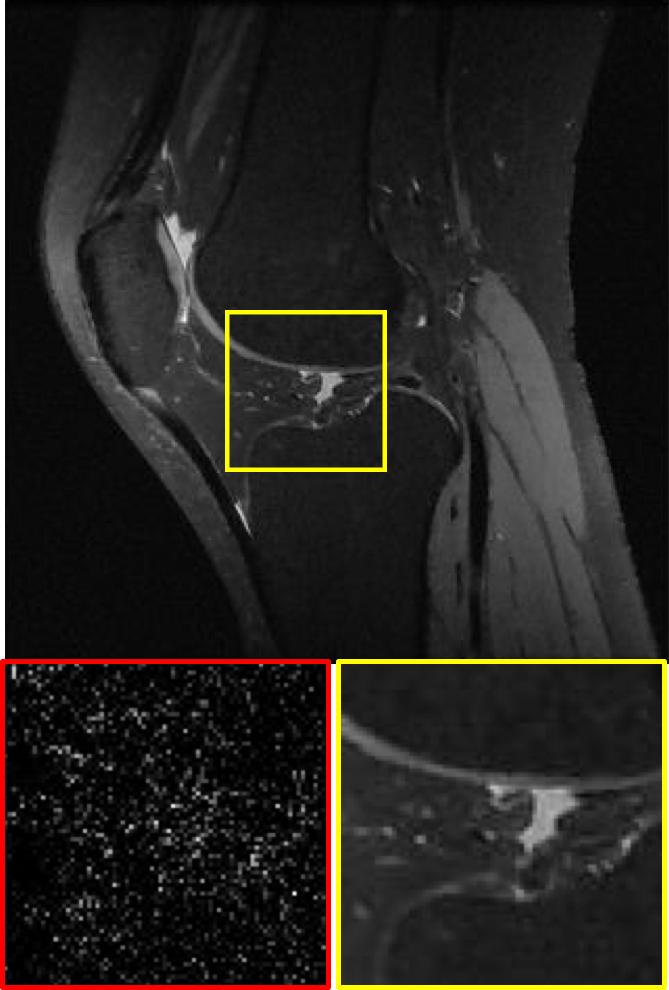

CS MR measurement matrix

LDAMP SURE was applied to CS-MRI reconstruction problem to demonstrate its generality and to show its performance on images that contain structures different from natural image dataset. We compared LDAMP SURE with state-of-the-art BM3D-AMP-MRI algorithm [16] for CS-MR image reconstruction along with TVAL3, BM3D-AMP, and dictionary learning method or DL-MRI [34]. Average image recovery PSNRs and run times are tabulated in Table 3. Figure 5 shows that our proposed method yielded state-of-the-art performance, close to the ground truth. The results reveal that proposed LDAMP SURE-T outperforms existing algorithms in all sampling ratios.

Ground truth

TVAL3

BM3D-AMP

NLR-CS

LDAMP SURE

LDAMP SURE-T

Ground truth

TVAL3

BM3D-AMP

DL-MRI

BM3D-AMP-MRI

LDAMP SURE-T